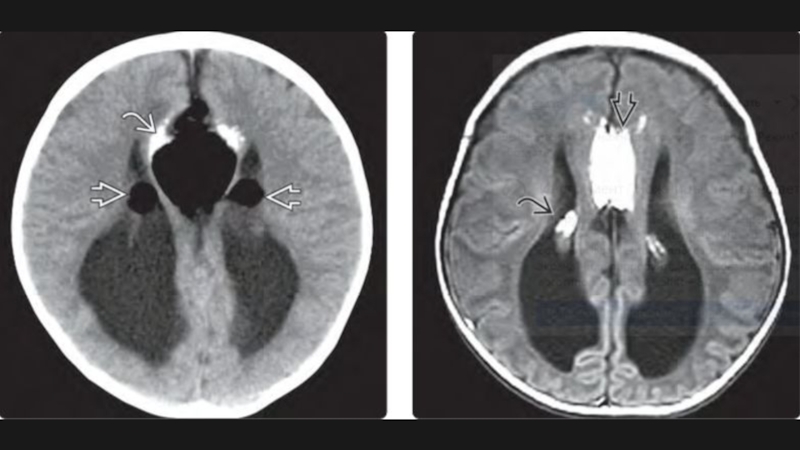

Слайд 23Алобарная голопрозэнцефалия

Алобарная голопрозэнцефалия

Слайд 24Голопрозэнцефалия

Неполное разделение полушарий головного мозга

Визуализация: -единственный желудочек

-отсутствие или частичное базальное и полушарное расщепление в сочетании с отсутствием/неполным развитием межполушарной борозды/серпа мозга

-непарная передняя мозговая артерия

Выраженность и тяжесть аномалии определяется

степенью расщепления переднего мозга

алобарная ГПЭ

семилобарная ГПЭ

лобарная ГПЭ

ГолопрозэнцефалияНеполное разделение полушарий головного мозгаВизуализация: -единственный желудочек